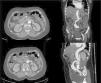

En este artículo presentamos un caso de una DA espontánea aguda de aorta abdominal infrarrenal asociada a un aneurisma de aorta abdominal, y que se intervino de forma quirúrgica en diciembre de 2013. La paciente en cuestión es una mujer de 72 años, hipertensa (HTA), dislipémica, con fibrilación auricular anticoagulada con «davigatrán», cardiopatía hipertensiva con una fracción de eyección conservada y una insuficiencia aórtica leve-moderada. La mujer acudió a urgencias por un cuadro de 9 días de evolución de dolor lumbar inespecífico, por lo que fue dada de alta con tratamiento analgésico ante la sospecha de cólico nefrítico. Debido a la persistencia del dolor, y a pesar del tratamiento, acudió al cabo de un día, de nuevo, a urgencias donde se realizó angio-TAC que objetivó una DA aguda a nivel abdominal infrarrenal con un AAA de 37mm, con falsa luz, que llega a nivel proximal a la altura del tronco celíaco sin englobar ninguna arteria visceral. Distalmente, la luz falsa progresa sin trombosis a las arterias ilíacas (fig. 1). La paciente se encontraba hemodinámicamente estable, y a la exploración física presentaba pulsos distales y exploración abdominal anodina. Ante los hallazgos radiológicos se decidió realizar cirugía abierta urgente mediante bypass aorto-bifemoral con clampaje suprarrenal y reimplante de la arteria renal izquierda, previa instilación de suero Ringer frío en ambos riñones. En la intervención se fijó la capa íntima en todas las anastomosis (fig. 2A-C).

Angio-TC: Aneurisma de aorta abdominal infrarrenal de 37mm con disección aguda, que progresa distalmente con ambas luces permeables hasta arterias ilíacas externas, y progresa proximalmente con falsa luz trombosada hasta nivel del tronco celíaco. No se observa disección a nivel de aorta torácica, cuyo diámetro a nivel distal es de 33,7mm.